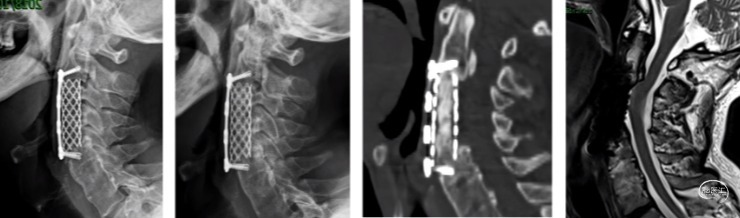

后纵韧带骨化:椎体次全切ACCF

整体迁移融合技术ACAF